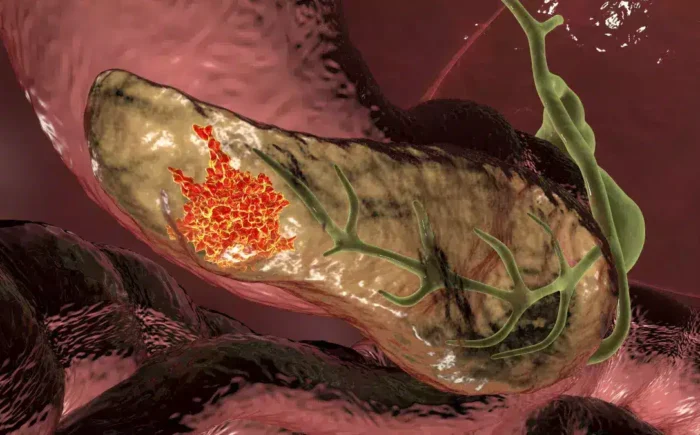

CÁNCER DE PÁNCREAS SERÁ LA SEGUNDA CAUSA DE MUERTE ONCOLÓGICA EN LOS PRÓXIMOS AÑOS: ESPECIALISTAS

El cáncer de páncreas registra un crecimiento sostenido en el mundo y, de acuerdo con especialistas, en los próximos cinco años se convertirá en la segunda causa de muerte oncológica, debido a que la mayoría de los pacientes son diagnosticados en etapas avanzadas.

Se trata de una de las enfermedades más desafiantes por su diagnóstico tardío y su alta agresividad. Tan solo en 2022 se estimaron 510 mil 992 nuevos casos a nivel global. En el Servicio de Oncología y Endoscopía del Antiguo Hospital Civil de Guadalajara “Fray Antonio Alcalde”, entre 2018 y 2024 se registraron 3 mil 344 lesiones sólidas de páncreas, de las cuales 75 por ciento correspondieron a cáncer.

La médica endoscopista Ana Isabel Tornel Avelar detalló que este padecimiento “es la sexta causa de muerte por cáncer en el mundo y ocupa el lugar número 12 en incidencia global; en México representa la séptima causa de muerte por cáncer. En los últimos 25 años, la incidencia aumentó 55 por ciento, la prevalencia 63 por ciento y la mortalidad 53 por ciento”.

A partir de 2030, el cáncer de páncreas se proyecta como la segunda causa de muerte oncológica. Entre los principales factores de riesgo se encuentran el consumo de tabaco, ingesta excesiva de alcohol, mutaciones genéticas, síndromes hereditarios, edad avanzada y diabetes de larga evolución.